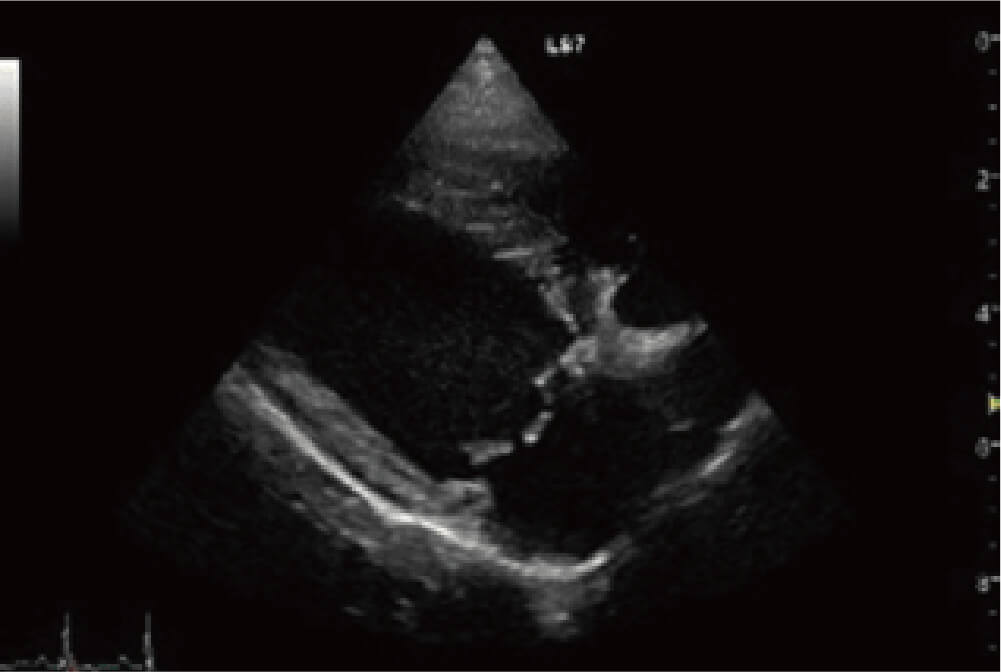

左図は僧帽弁形成術前の心臓超音波画像(右傍胸骨長軸四腔断面像)。Carpentier’s functional classification typeⅡの特徴である弁尖の逸脱が前尖・後尖共に見られます。またカラードプラ画像では重度の僧帽弁逆流がみられます。